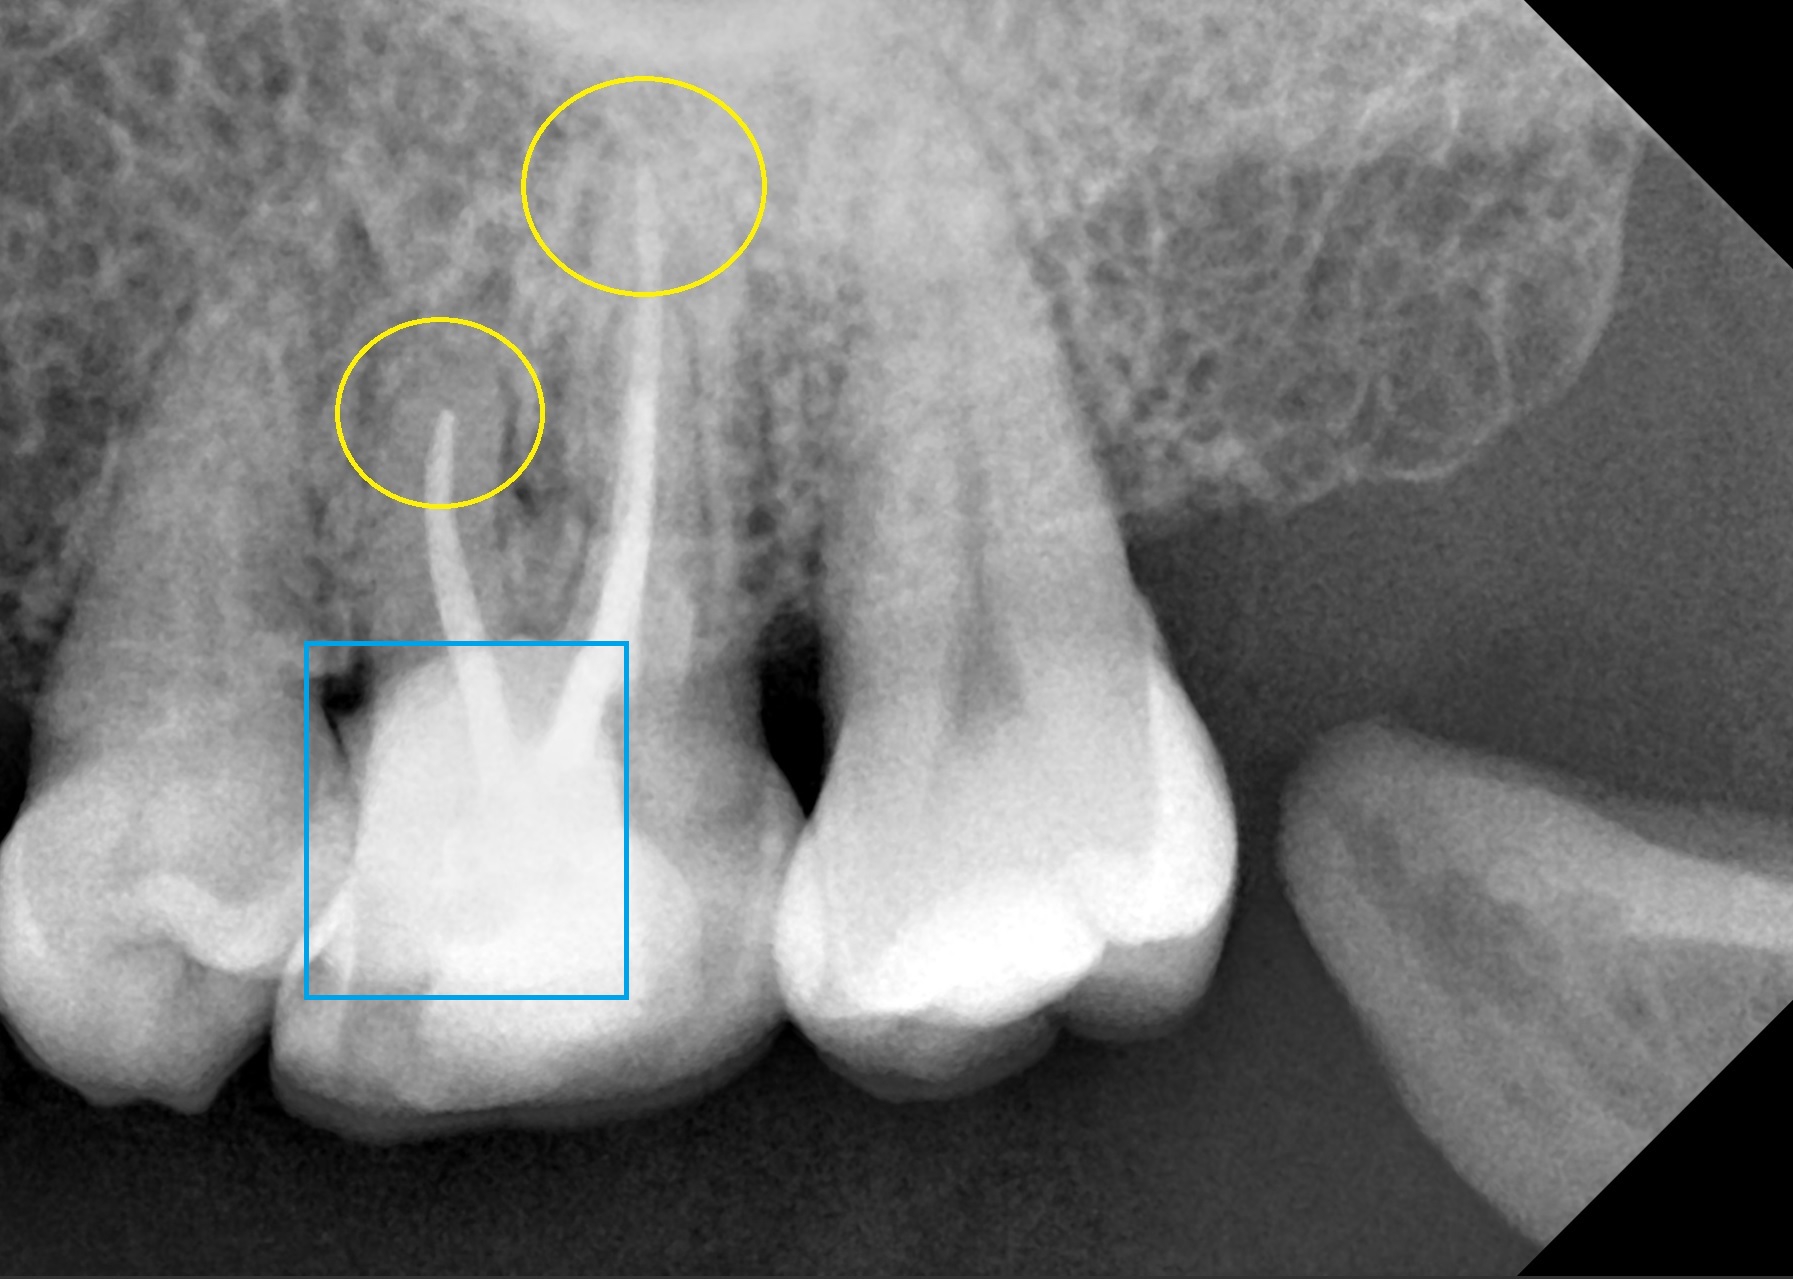

환자분께선 3번의 내원을 통해 신경치료를 마무리하였으며, 노란색 원형 부위를 보면 이전 포스팅에서 말씀드린바, (바로가기) 모든 근관 끝까지 신경 치료용 재료인 Gutta-percha 와 MTA가 잘 채워진 것을 확인하였습니다.

또한 파란색 사각형 부위를 보면 제거해냈던 치아 파절편 부위를 잇몸 하방까지 Glass-ionomer라는 치아 수복용 재료로 채워서 마무리하였습니다.